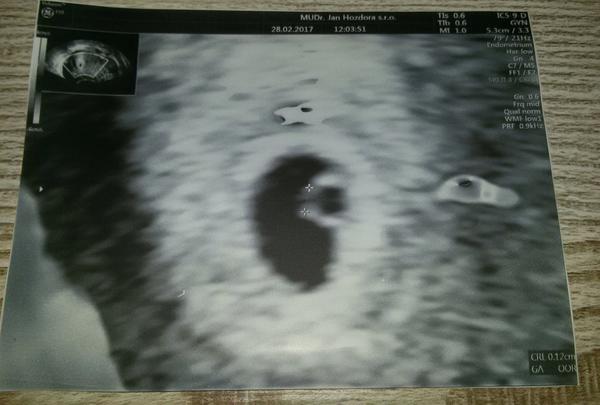

@arielka222 jsi strasne hodna me rekl jen ten 5+2 ze CRL coz nevim co je meri 0.12cm a vcera 5+4 mi rekl ze se mu zda ze to povyrostlo ale neni ram srdecni akce..to je napred zloutkovy vacek a neni ani emvryjko?embryjko je az se srdickem?

@arielka222 a jeste rikal v to utery 5+2 ze mei 1.8 asi milimetru..vubec to nechapu totiz.

@arielka222 vcera zadne cisla nerikal..

Toto je ma fotka 5+2

Vypada to jako prstynek a jdou videt 2 křizky ze neco měril..